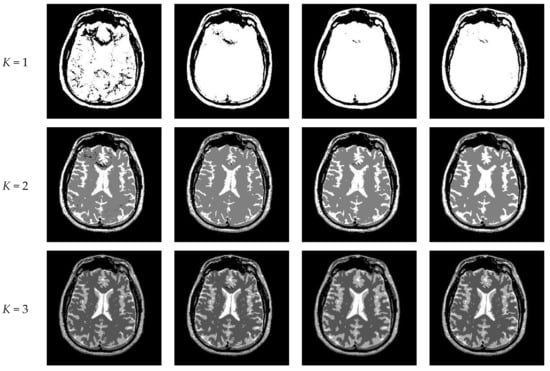

Figure 10 and Figure 11 display segmentation results of different algorithms for slice #042 and slice #082, respectively. For single level of thresholding K = 1, it can be observed that segmentation results obtained by the Otsu method have many fragmented small areas, such as the lower soft tissue in the first row of Figure 10a, whereas IIMT performs slightly better. However, the edges segmented by HL-IIMT and Proposed are much clearer. In the case of , it can be seen that Otsu and IIMT have similar segmentation effects. HL-IIMT and Proposed are better than Otsu and IIMT in terms of edge-preserving and denoising, as shown in the segmentation results in Figure 11 (K = 2, K = 4).

Figure 11.

Segmentation results obtained by different segmentation algorithms for slice #082 with number of thresholds K from 1 to 5: (a) Otsu, (b) IIMT, (c) HL-IIMT, (d) Proposed.